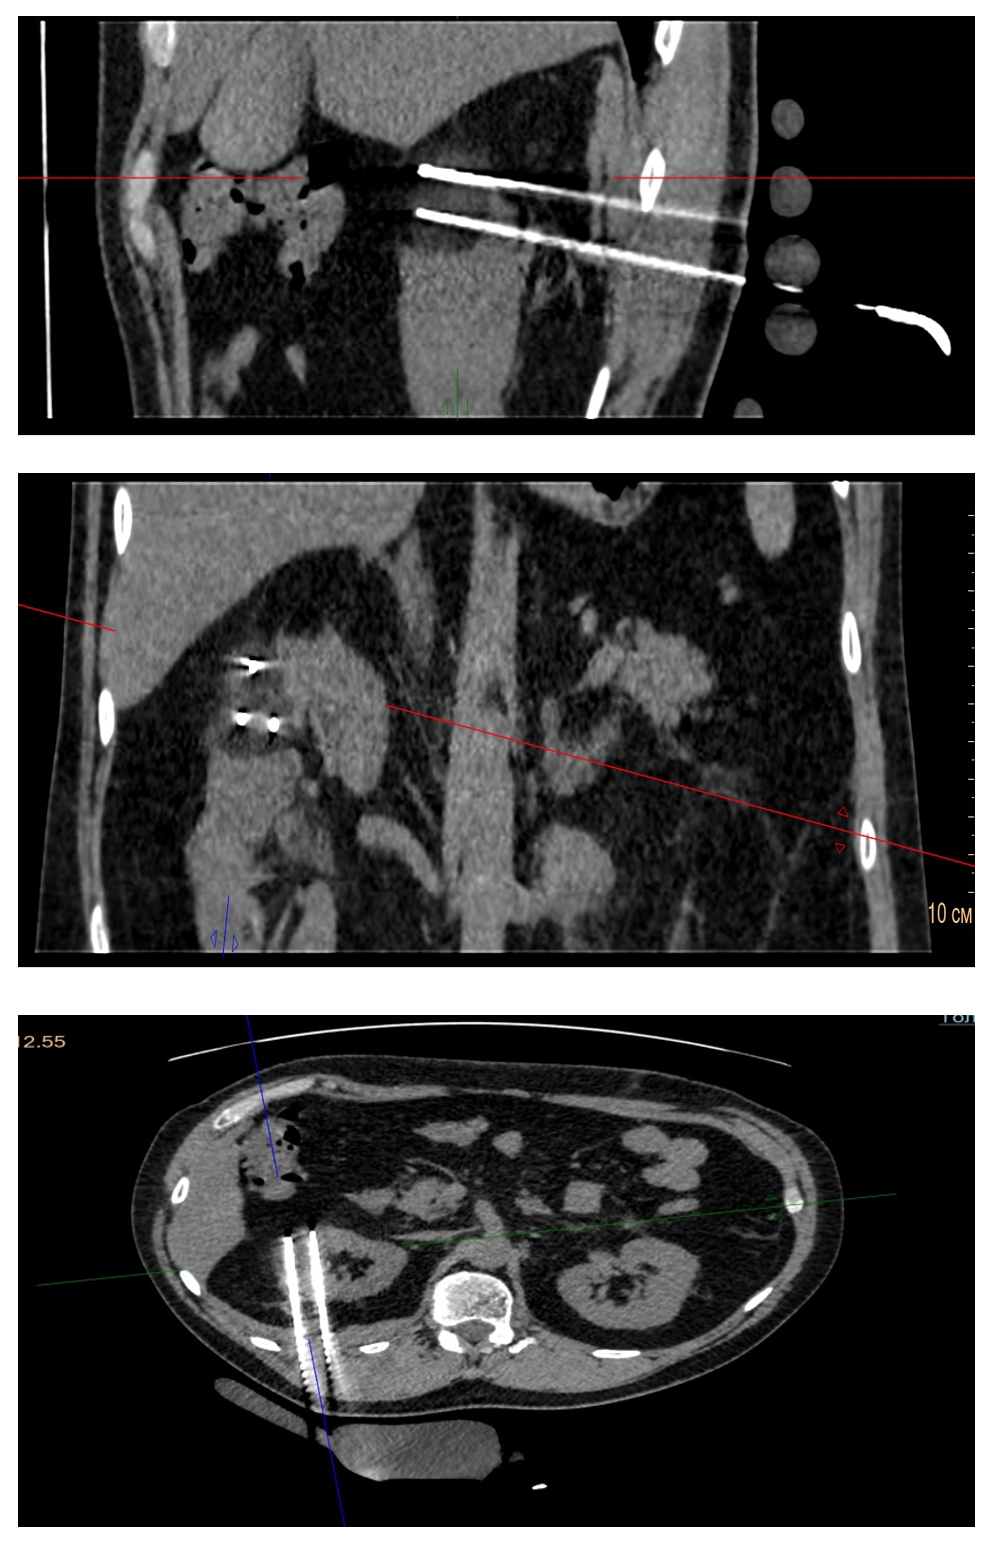

Выполнена 13.01.2025 чрескожная криоаблация опухоли правой почки с одномоментной биопсией под местной анестезией (рис.2) (гистологическое заключение № 8538-39/25: в биоптате светлоклеточная карцинома G1). Для выполнения хирургического вмешательства использовалась система навигации для биопсий SIRIO, для криоаблаци применен аппарат 3-го поколения SeedNet Gold, производства компании Galil Medical. Маленький размер игл и вариабельный объем заморозки обеспечивает достаточно точный захват опухоли или органа-мишени с минимальным воздействием на здоровые ткани. Криоаблация проведена 3-мя циклами, каждый из которых включал 15 минут заморозки и 10 мин оттаивания (пассивное с чередованием активного).

Рисунок 2 - Послеоперационный период